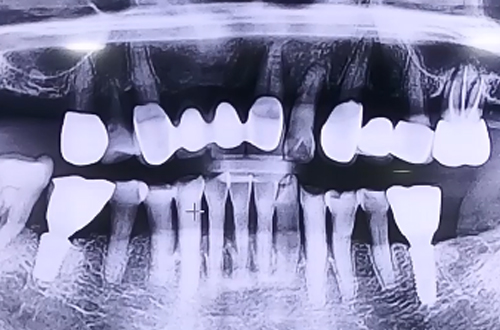

BEFORE

오른쪽 위 가장 안쪽에 있는 어금니에 임플란트를 진행한 환자분이십니다.

상악동에 임플란트가 빠지지 않도록 뼈 없는 공간에 뼈를 올려주면서 상악동거상술과 뼈이식을 이용하여 임플란트 치료를 진행해 드렸습니다.